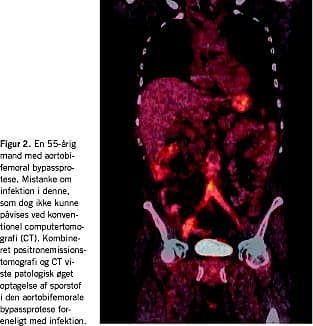

Inficerede karproteser

Infektion i karproteser er en sjælden, men potentielt livsfarlig komplikation efter vaskulær rekonstruktion. Symptombilledet er ofte uspecifikt. CT er veletableret som førstevalg, men har visse begrænsninger, specielt i tidlige stadier (Figur 2 ). MR har været foreslået, men har ikke fundet sin endelige plads [6]. Leukocytskintigrafi har generelt en sensitivitet > 90% og en specificitet lige under 90%. Kasuistikker har vist positive resultater med FDG PET, og enkelte større studier har været lovende, men den tilbagevendende problemstilling er sparsomme anatomiske oplysninger og et relativt højt antal falsk positive resultater, særligt i den tidlige postoperative fase hvor omtrent 40% af infektionerne forekommer. Referencestandarden har indtil videre været leukocytskintigrafi, men PET og PET/CT spås en betydelig rolle [7].

For nylig publiceredes det første konsekutive studie med FDG PET/CT hos 39 patienter mistænkt for karproteseinfektion [8]. Referencen var histopatologi og/eller mikrobiologi og/eller konsensus ud fra tilgængelige kliniske data, og tolkning af PET/CT-billederne skete ublindet. Studiet opgjorde sensitivitet, specificitet, positiv prædiktiv værdi og negativ prædiktiv værdi til henholdsvis 93%, 91%, 88% og 96%. Artiklen understregede, at styrken ved PET/CT er den præcise differentiering mellem infektion i karprotesen og i det omkringliggende væv, der bliver mulig på grund af kombinationen af detaljerede anatomiske oplysninger og fundet af metabolisk aktivt væv.